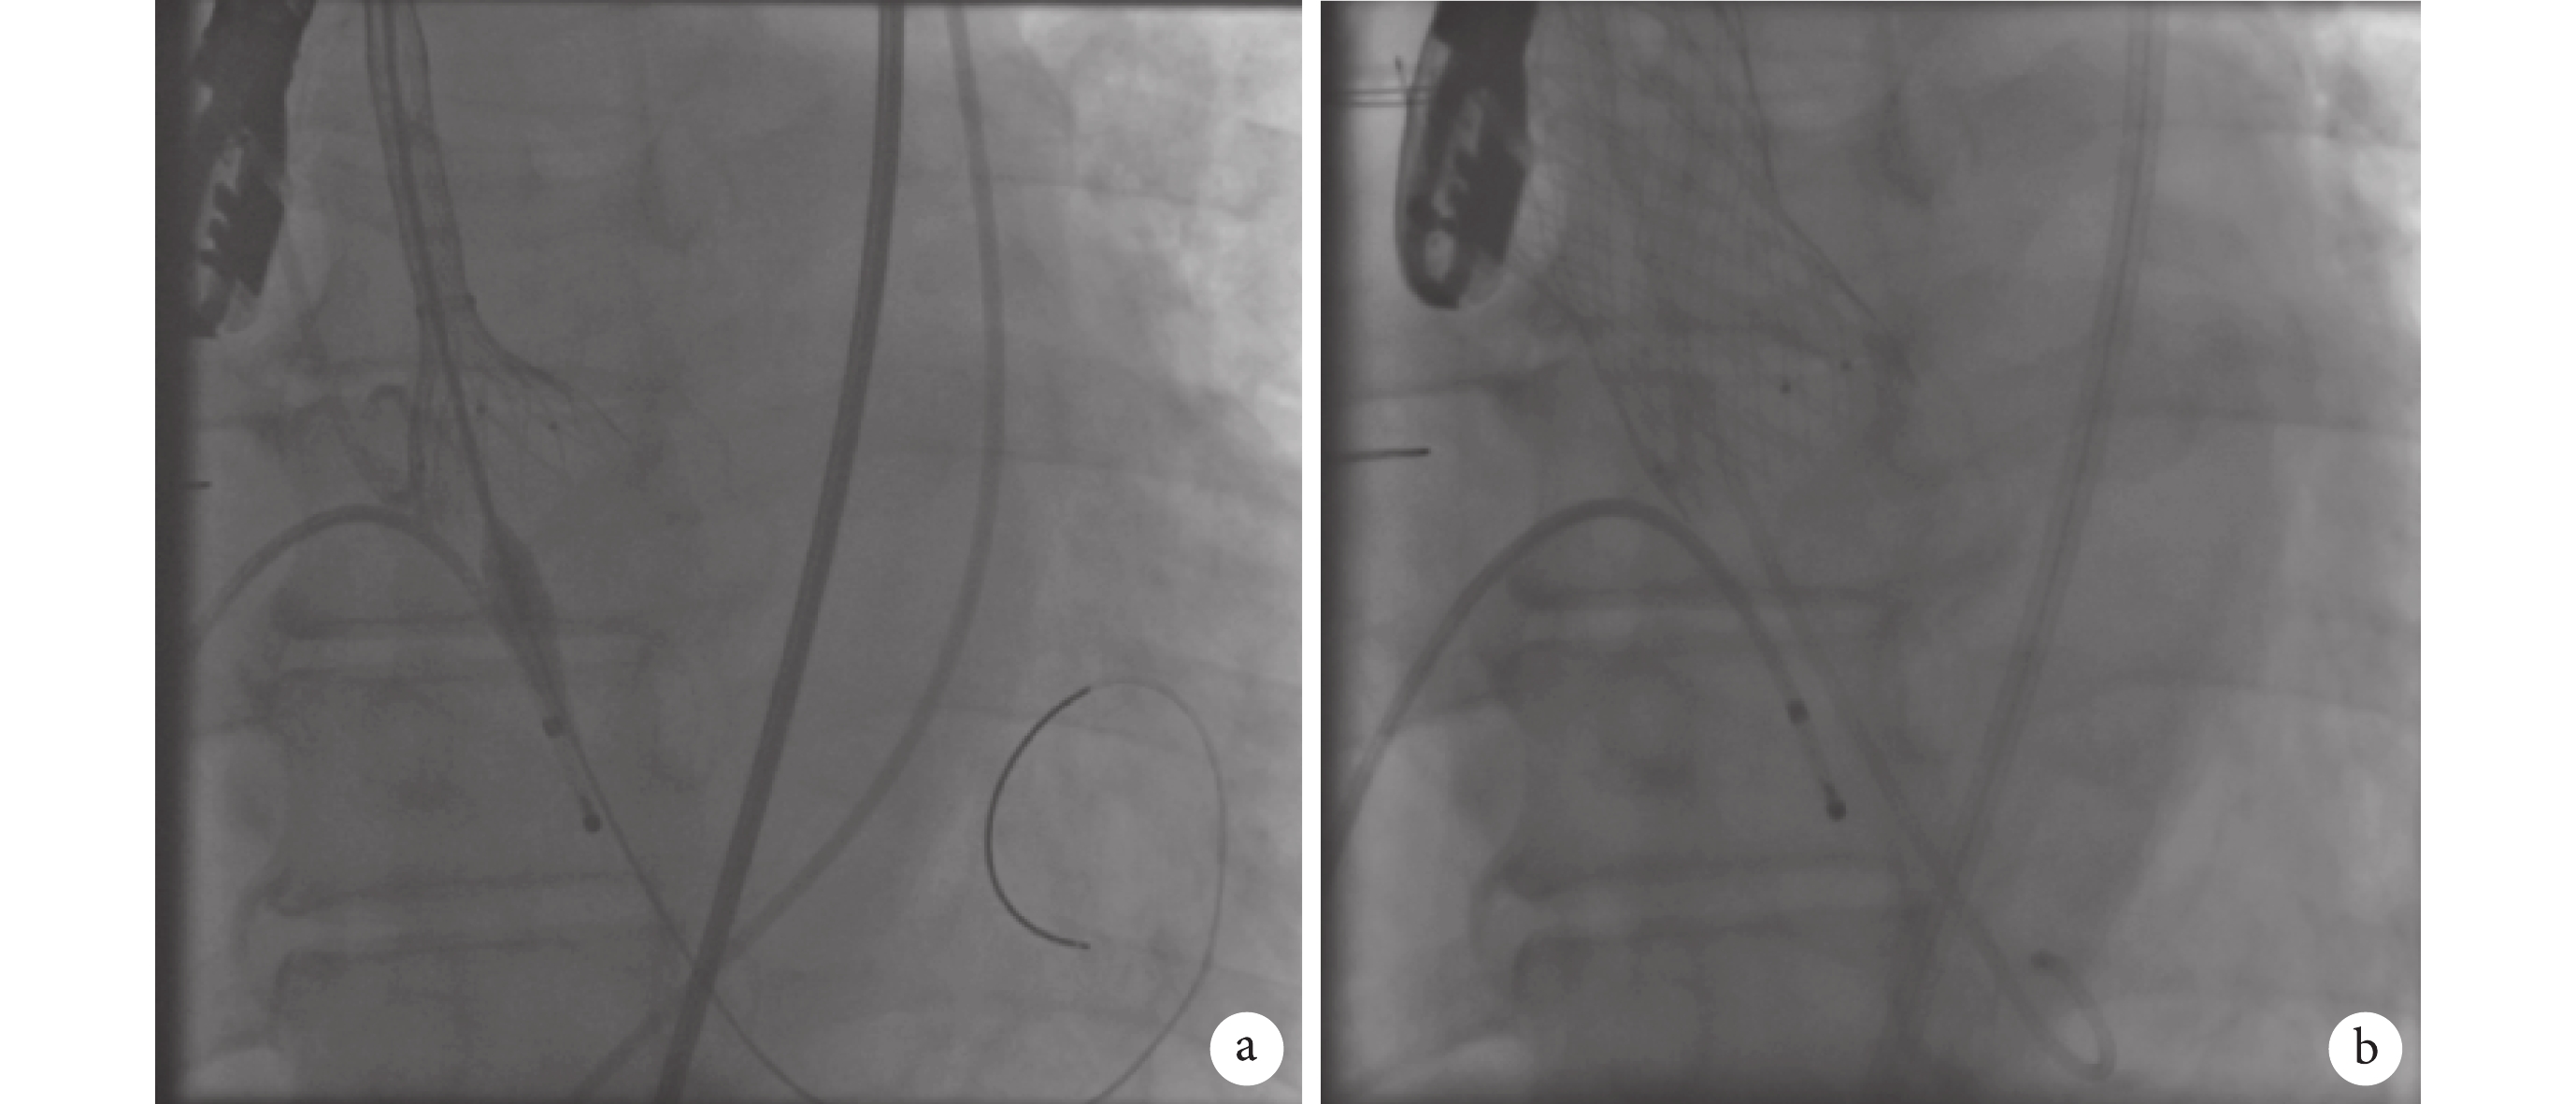

2019 年 10 月 10 日 8 時開始手術。手術過程:根據主動脈 CTA,選擇左側股動脈為主入路。給予靜脈麻醉后行氣管插管成功,同時給予超聲指導下左側股動脈神經阻滯下麻醉,建立右橈動脈有創壓力監測通道。同時建立右側頸內靜脈下行中心靜脈置管。行 TEE,測量患者術前數據,測得 LVEF 為 19.7%(圖 2)。雙側腹股溝區、下腹部前胸部常規消毒、鋪巾。于左右股骨頭骨性標志透視下沿股動脈走行穿刺后,分別先后送入 4F、6F 股動脈鞘管。經右側股動脈鞘管,經 0.035 英寸 J 型導絲(直徑 0.89 mm)送入 6F 彎頭豬尾導管至升主動脈監測中心動脈壓力并協助瓣膜定位。行右側股靜脈穿刺,置入 6F 動脈鞘放置臨時起搏器于右心室心尖部。左側股動脈 Proglide 預縫合,更換 10F 鞘管,AL2 導管指引下直頭導絲跨瓣,沿導絲送入 AL2 導管至左心室,交換為 6F 豬尾導管,主動脈和左心室測壓。經豬尾導管換 COOK TSMG 加長加硬導絲,調整導絲處于左心室滿意位置,退出豬尾導管,經導絲換為 19F 鞘。根據術前 CT 測量結果,選擇 Venus-A 29 mm 瓣膜。經鞘管送入 Venus-A 29 mm 瓣膜輸送系統至主動脈瓣環處,行主動脈根部造影,調整輸送鞘位置,使瓣膜的深度剛好在主動脈瓣瓣環水平,擬 0 位釋放,然后固定輸送鞘,起搏器未起搏,開始釋放瓣膜(圖 3a)。當確認瓣膜處于理想位置后,完全釋放瓣膜(圖 3b)。退出主動脈瓣膜輸送系統;豬尾導管行主動脈根部造影顯示:人工瓣膜位置合適、開合良好,冠狀動脈開口未受影響。瓣膜釋放后 TEE 示瓣膜位置良好,輕度瓣周漏,中心微量反流,無心包積液,前后即刻 TEE 顯示跨瓣壓差較術前明顯改善(圖 4)。血流動力學監測顯示術后跨瓣壓差接近 0 mm Hg(圖 5)。術中患者透視下心臟收縮乏力,血壓低,給予較大量升壓藥物維持,血流動力學相對穩定,瓣膜釋放后血壓 120/80 mm Hg,心率 95 次/min 左右,為房顫心律,未見房室傳導阻滯。造影提示雙側股動脈未見滲血及夾層,退出鞘管、導絲。左右側股動脈均予 Proglide 縫合器縫合。包扎雙側術區。術中共用造影劑 120 mL。手術結束。患者脫機后呼吸偏弱,血氧飽和度略低,帶氣管插管,抱球呼吸下送回心臟監護病房。

a. TAVR 術中未起搏釋放瓣膜;b. TAVR 術中瓣膜完全釋放